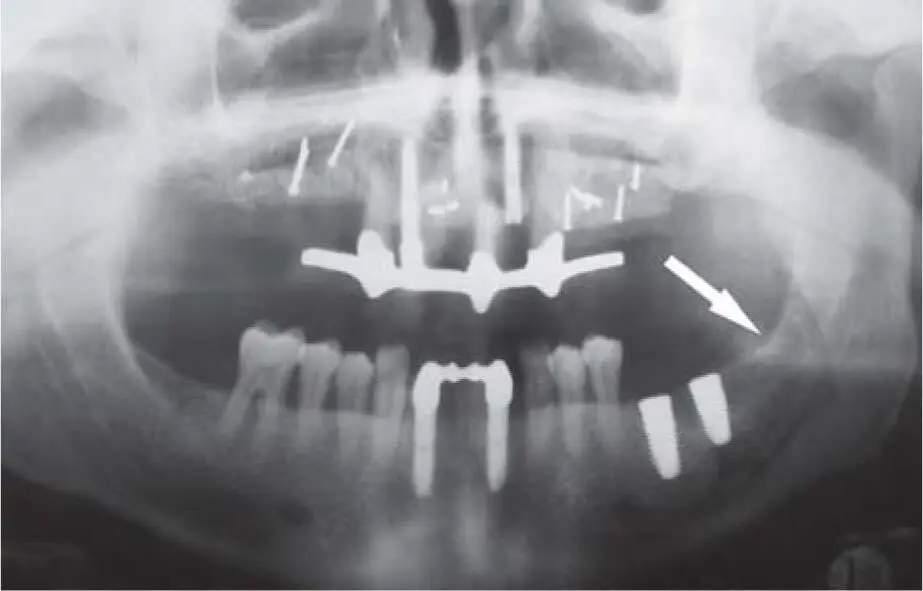

Fig 222ePanoramic radiograph documenting a bilateral vertical bone - фото 123

Fig 2-22ePanoramic radiograph documenting a bilateral vertical bone augmentation in the right and left posterior mandible. The right bone graft is very close to the antagonist elongated second molar.

Fig 222fPanoramic radiograph documenting the implant insertion after reducing - фото 124

Fig 2-22fPanoramic radiograph documenting the implant insertion after reducing the graft volume. An endodontic treatment was also performed on the antagonist elongated tooth after reducing its volume.